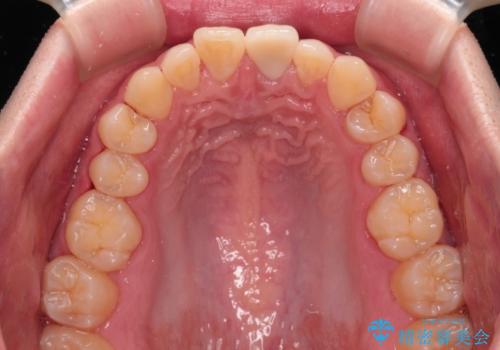

変色した前歯をオールセラミッククラウンに

- 転んだ際に欠けてしまった前歯の変色が気になるとのことで来院された患者様です。

診察やレントゲン写真より神経組織の失活が認められたため、根管治療、ファイバーコアによる土台築製後、オールセラミッククラウンにて補綴することとしました。